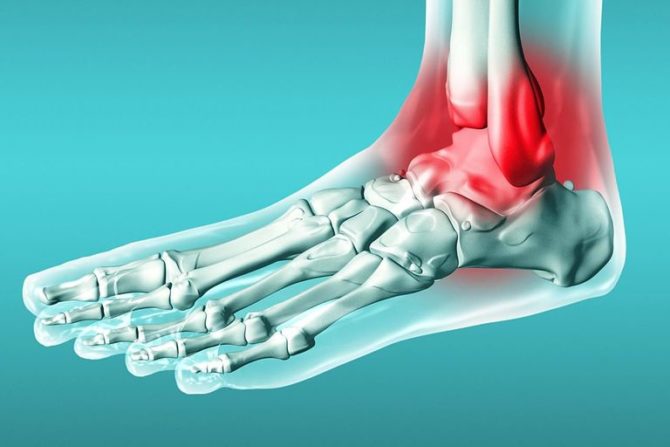

Что такое синовит голеностопного сустава, как он выражается? Это воспалительный процесс, происходящий во внутренней оболочке суставной сумки и характеризующийся скоплением жидкости в полости сустава. Синовиальная оболочка выстилает всю внутреннюю часть суставной сумки и выполняет важные функции. В первую очередь она обеспечивает защиту суставных структур от внешних повреждений, выполняет амортизационную функцию и улучшает подвижность сустава.

При воспалении, или синовите, происходит избыточное выделение внутрисуставной жидкости. Это нарушает нормальное питание суставных структур и приводит к дегенеративно-дистрофическим процессам в них. Данная патология, как правило, в одноименных суставах наблюдается только с одной стороны. Лечение болезни зависит от причины ее возникновения. Помощь оказывают различные специалисты — ортопед, ревматолог, гематолог.